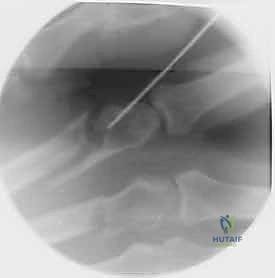

خطوات التثبيت الجراحي - توثيق بصري (Intraoperative Imaging)

يحرص الدكتور هطيف على توثيق خطوات العمل الجراحي لضمان أعلى مستويات الدقة. نستعرض هنا مجموعة من الصور من داخل غرفة العمليات توضح مدى تعقيد ودقة هذه الجراحات:

تتطلب الجراحة انتباهاً خاصاً للأوتار الباسطة والقابضة والأعصاب الدقيقة المحيطة بالعظام. استخدام تقنيات الجراحة الميكروسكوبية (Microsurgery) يضمن عدم الإضرار بهذه الأنسجة الحساسة.

3. التثبيت باستخدام المسامير النخاعية (Intramedullary Nails/Wires)

في بعض كسور عنق العظمة المشطية (مثل كسر الملاكم)، يمكن إدخال سلك أو مسمار مرن داخل النخاع العظمي. هذه التقنية ممتازة للحفاظ على طول العظمة وتصحيح الزاوية دون الحاجة لفتح جراحي كبير.